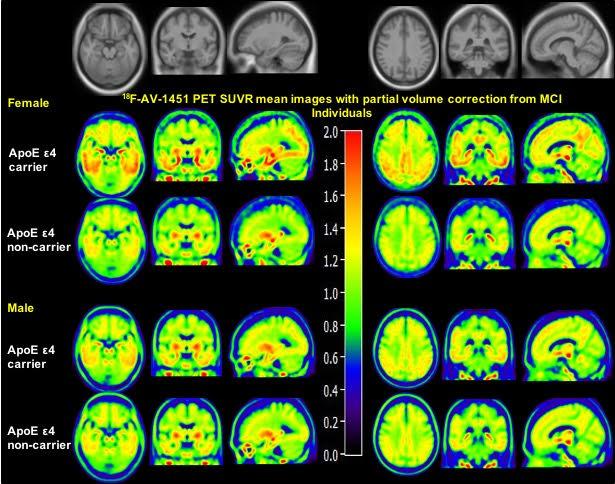

The strongest genetic risk factor for Alzheimer's disease is the apolipoprotein E type 4 allele (ApoE ε4). Research presented by Manish Paranjpe at the 2019 Annual Meeting of the Society of Nuclear Medicine and Molecular Imaging (SNMMI) used positron emission tomography (PET) to show that women who are ApoE ε4 carriers and already experiencing mild cognitive impairment are more susceptible than men to tau accumulation in the brain.

"Sex plays an important role in Alzheimer's disease risk, with females having a higher lifetime risk of developing the disease and an increased vulnerability to genetic risk factors," points out Yun Zhou, who led the project at the Mallinckrodt Institute of Radiology, Washington University in St. Louis School of Medicine. He explains, "This is the first study to demonstrate that sex modulates the effect of ApoE ε4 on brain tau depositing, measured using 18F-AV-1451-PET imaging, in the entorhinal cortex, amygdala, parahippocampal gyrus, and posterior cingulate of the brains of patients with mild cognitive impairment (MCI). Strikingly, females experience greater ApoE ε4-associated increases in brain tau deposition in these regions compared to their male counterparts."

This cross-sectional study involved 131 cognitively normal (CN) elderly controls (66 women) and 97 MCI subjects (39 women) from the Alzheimer's Disease Neuroimaging Initiative (ADNI) database. The mean age of all was 77. Preprocessed 18F-AV-1451 PET images, T1-weighted structural MRI scans and demographic information were included. After downloading pre-processed images from ADNI, a partial volume correction method was applied on all PET images (improving spatial resolution and contrast), and structural MRIs were used for PET spatial normalization. All statistical analyses were performed after controlling for baseline age and education.

Sex Modulates the ApoE ε4 Effect on 18F-AV-1451 Tau PET. (Credit: Paranjpe M, Liu M, Paranjpe I, et al.)

In addition to finding women with the ApoE ε4 mutation more susceptible than men to tau accumulation, Zhou notes: "Our study also confirmed that sex does not modulate the ApoE ε4-associated tau deposition in the brains of cognitively normal elderly individuals, and it extends our understanding of how sex modulates the ApoE ε4 effect on tau deposition in the brains of individuals at the early stage of Alzheimer's disease."